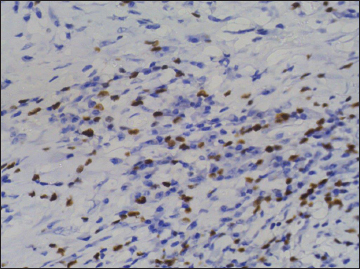

A 52 year-old nonsmoker, alcoholic male patient with spinocerebellar ataxia as comorbidity, presented in November 2016, with a complaint of progressive dysphagia of 2 months duration. Upper gastrointestinal endoscopy showed circumferential growth in lower-third of the esophagus with luminal narrowing. Computed tomography (CT) of thorax showed 13-mm thick circumferential mural thickening involving long segment of the lower esophagus causing marked luminal narrowing [Figure 1]. There was 3.5 cm × 2.5 cm mass in the subcarinal region, compressing esophageal lumen along with the few perigastric nodes [Figure 2]. Positron-emission tomography (PET)-CT showed intense fluoro-deoxy-glucose (FDG) avid thickening in the lower third of esophagus with FDG avid lower paratracheal, subcarinal, and perigastric nodes. Biopsy from the esophagus was done which was suggestive of moderately differentiated squamous-cell carcinoma [Figure 3]. The patient received neoadjuvant chemoradiation with 41.4Gy/23#/5 weeks by 3D-conformal radiation therapy technique along with five cycles of chemotherapy with injection paclitaxel 60 mg/m2 and injection carboplatin area under the curve 2 weekly. There was significant response to the treatment. Subsequently, the patient underwent thoracoscopic esophagectomy with gastric pull with feeding jejunostomy in February 2017. Histopathology showed minimal residual squamous-cell carcinoma of the esophagus with subcarinal node showing features of neuroendocrine tumor [Figure 4]. Subsequently, immunohistochemistry (IHC) was done to confirm the histopathological findings. IHC in esophageal blocks showed strong positivity for CK 5/6 [Figure 5], P63 [Figure 6], and epithelial membrane antigen [Figure 7] in tumor and surface epithelium with Ki67-30% [Figure 8], suggestive of residual small focus of squamous-cell carcinoma. IHC on subcarinal node was negative for CK5/6 and P63, strongly positive for synaptophysin [Figure 9] plus chromogranin [Figure 10], and weekly positive for CK7 [Figure 11], CK20 [Figure 12], and CDX2 [Figure 13]. Ki67 index was 4% [Figure 14], overall suggestive of atypical carcinoid tumor. There was no symptom related to endocrine overactivity or carcinoid syndrome. Follow-up PET-CT was normal, and hence the patient was kept on close follow-up, but at the time of writing the paper, the patient was untraceable.

| Figure 9 Immunohistochemistry on subcarinal node showing strong positivity for synaptophysin